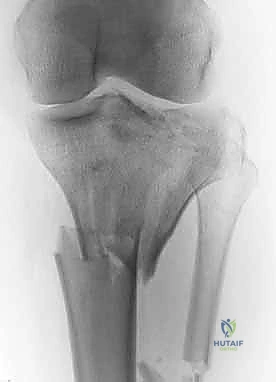

2. التصوير الإشعاعي (X-rays)

الخطوة الأولى هي التقاط صور أشعة سينية من عدة زوايا (أمامية خلفية، وجانبية). تعطي الأشعة السينية فكرة عامة عن وجود الكسر وموقعه، لكنها غير كافية لتقييم الكسور ثنائية اللقمة المعقدة.